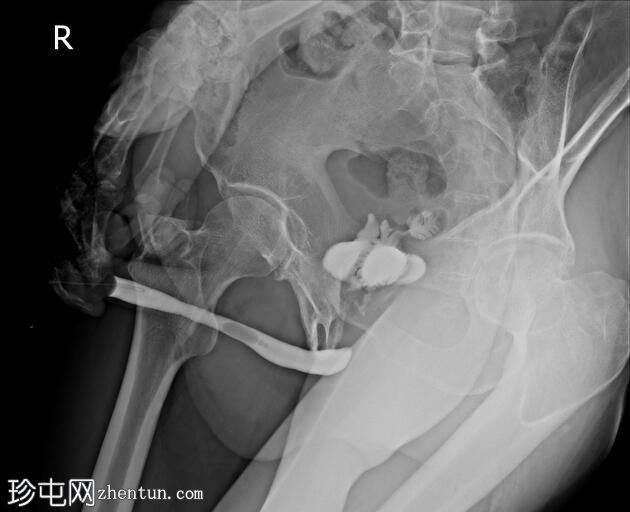

正位

斜位

前列腺部、膜部、球部及阴茎部尿道均正常。

造影剂经尿道注入,开始充盈具有肠袢特征的新膀胱。

该患者确诊为移行细胞癌后行膀胱切除术。治疗方案包括根治性膀胱切除术及新膀胱重建术。